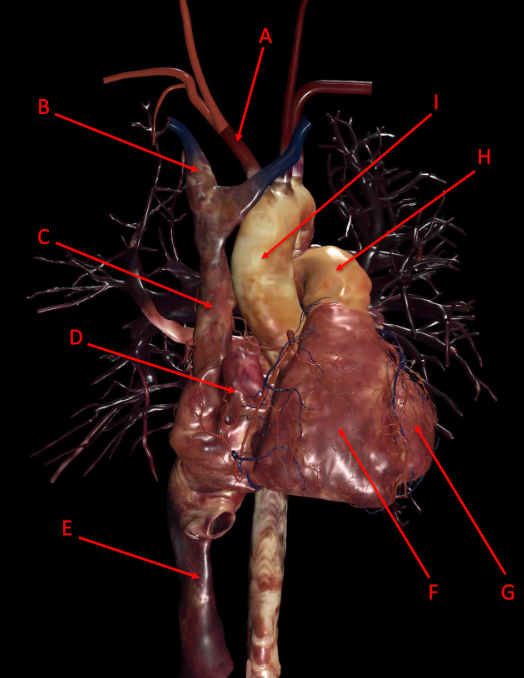

A

A. branchiocephalic trunk

B. Right Branchiocephalic vein

C. superior vena cava

D. right auricle

E. inferior vena cava

F. right ventricle

G. left ventricle

H. pulmonary trunk

I. aortic arch

J. left subclavian artery

K. left common carotid

L. right common carotid

M. right subclavian